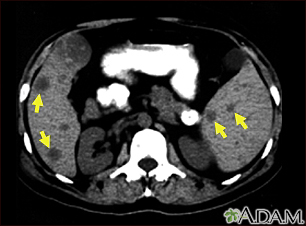

Spleen and liver metastases – CT scanBackSpleen and liver metastases – CT scanThis CT scan of the upper abdomen shows multiple tumors in the liver and spleen that have spread (metastasized) from an original intestinal cancer (carcinoma). E-mail FormEmail ResultsName:Email address:Recipients Name:Recipients address:Message: